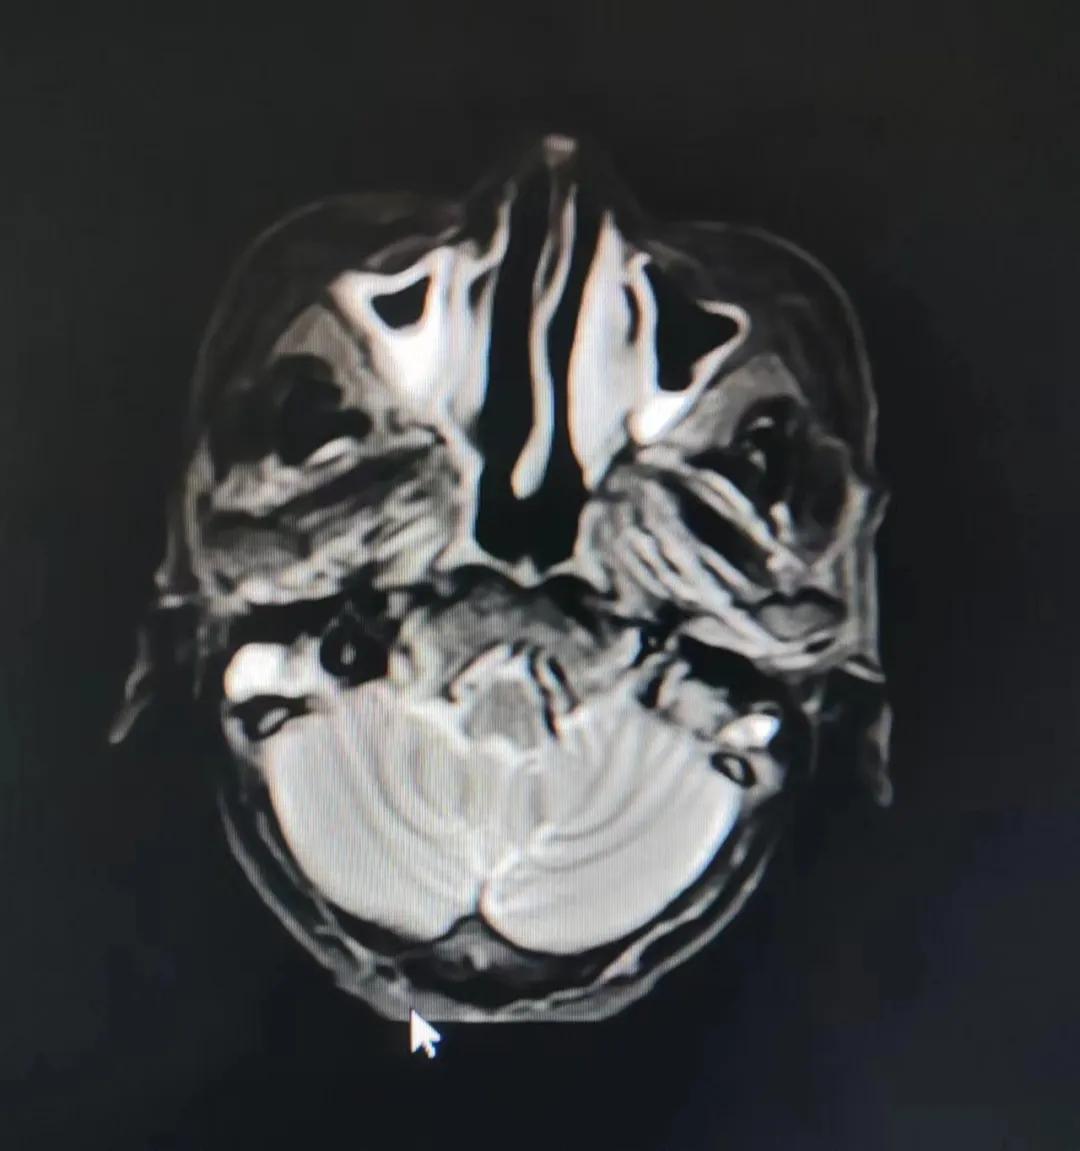

治療前

考慮到患者年齡較大、體質(zhì)差,手術(shù)難度大,且常規(guī)的放射治療難以保護患者晶體造成患者雙眼視力損傷,放療團隊以最快的速度制定了精準(zhǔn)放射治療方案并開始為其實施治療。僅僅數(shù)日后,老人腫塊出血即得到控制,腫塊明顯縮小,放療20次后腫塊迅速縮小!

治療后

放療結(jié)束,除了放療處的皮膚輕微放射性皮炎外,基本沒有什么不良反應(yīng)。復(fù)查發(fā)現(xiàn),鼻腔淋巴瘤已不可見,目前患者已康復(fù)出院。